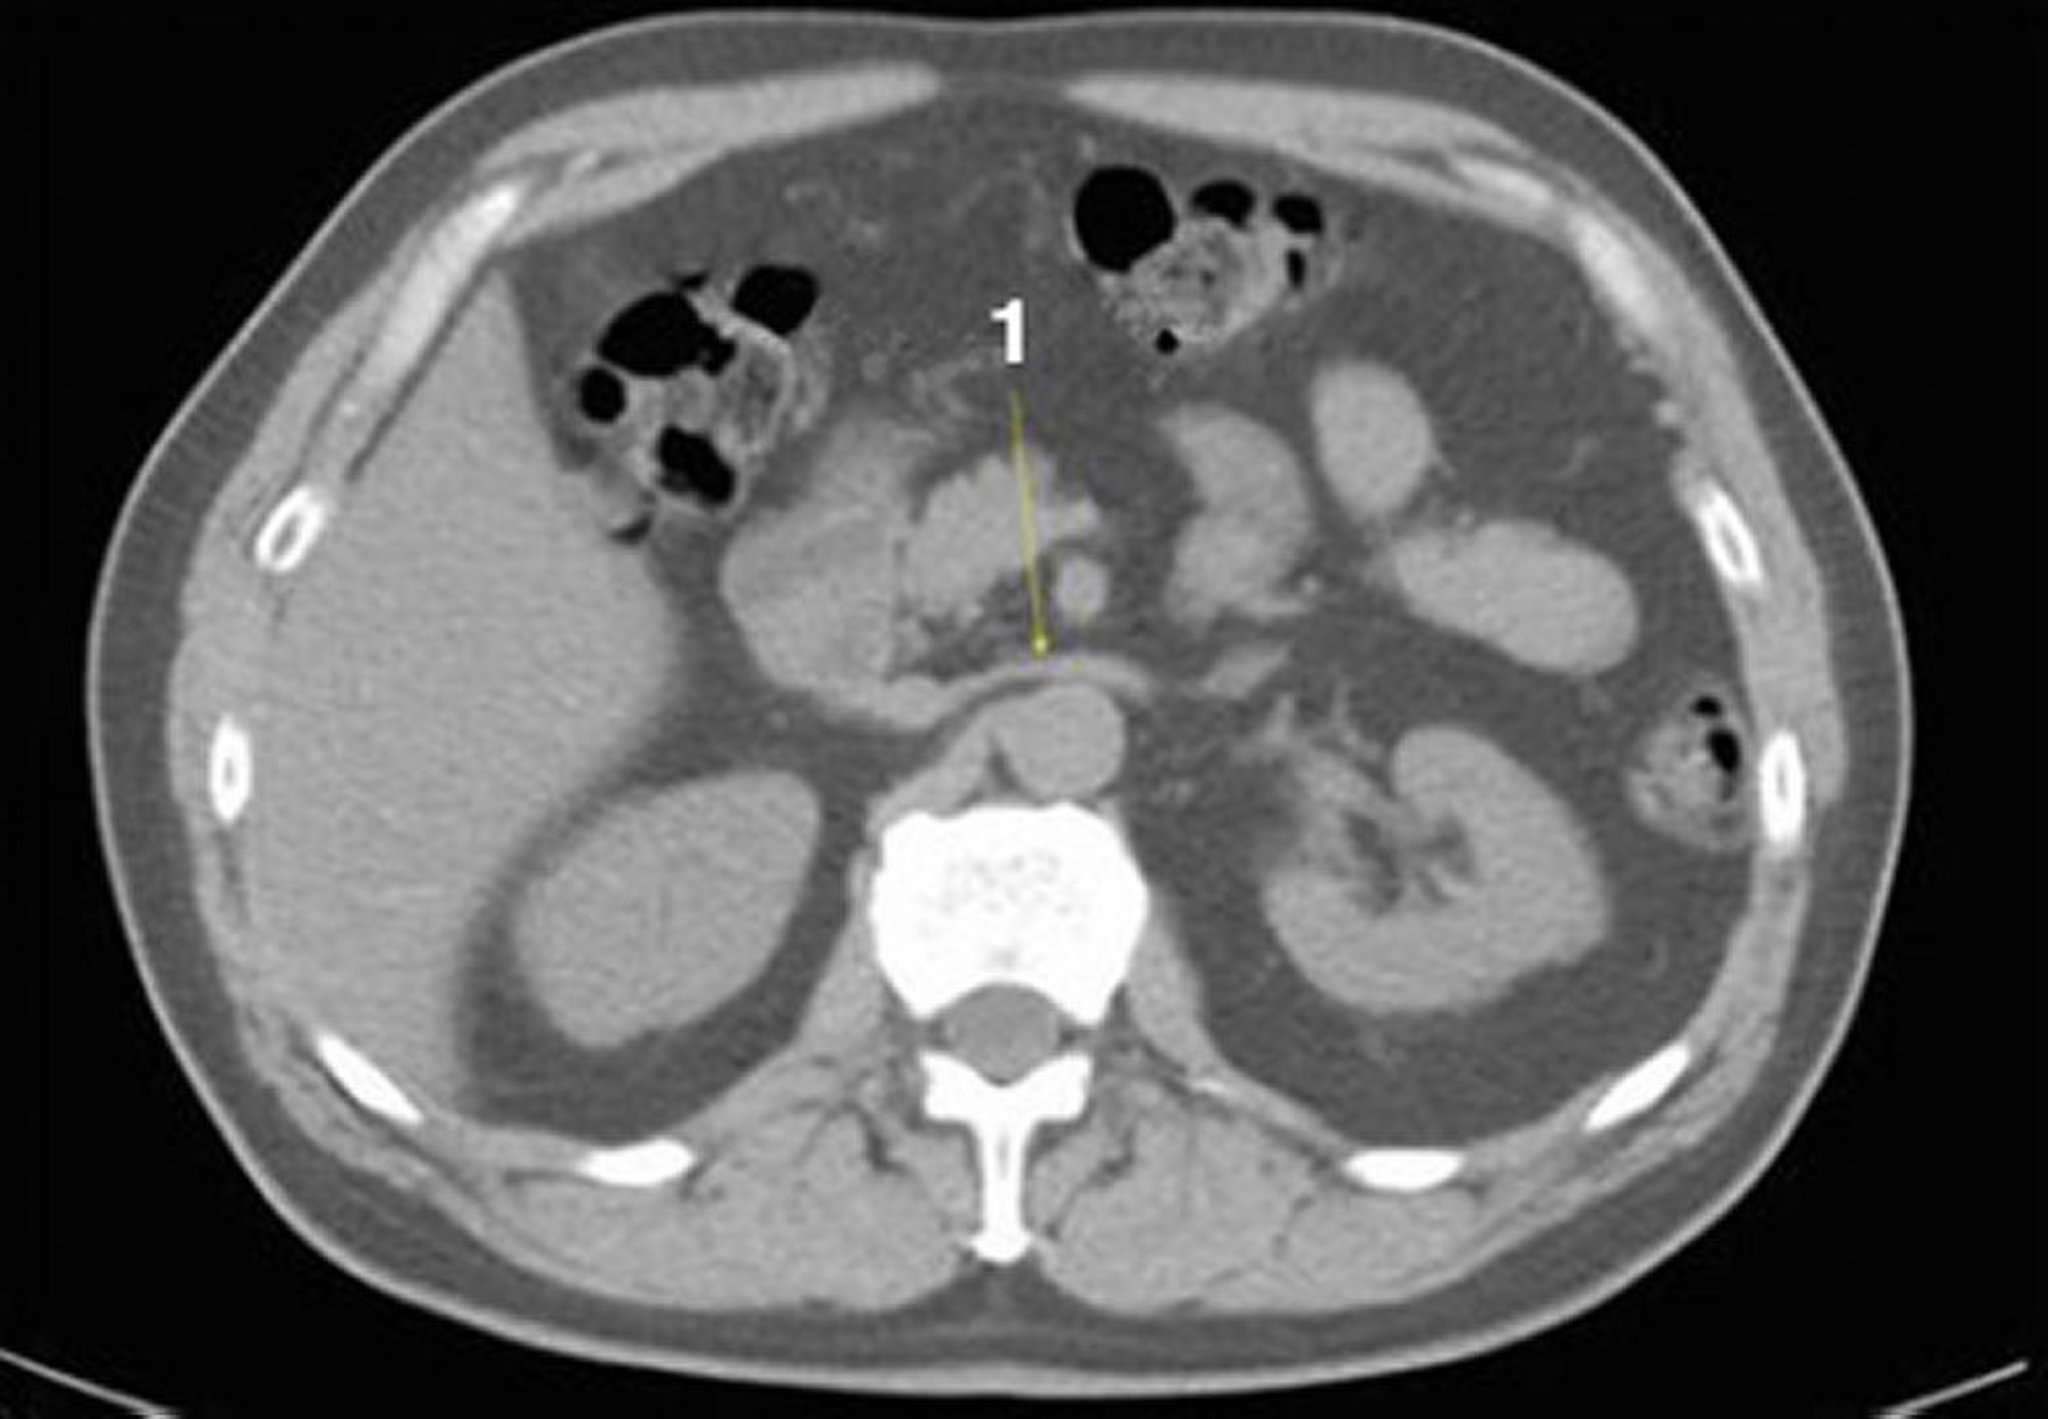

КТ органів черевної порожнини та малого тазу без контрастування, що демонструє нормальну анатомічну картину (слайд 12)

1 = left renal vein.